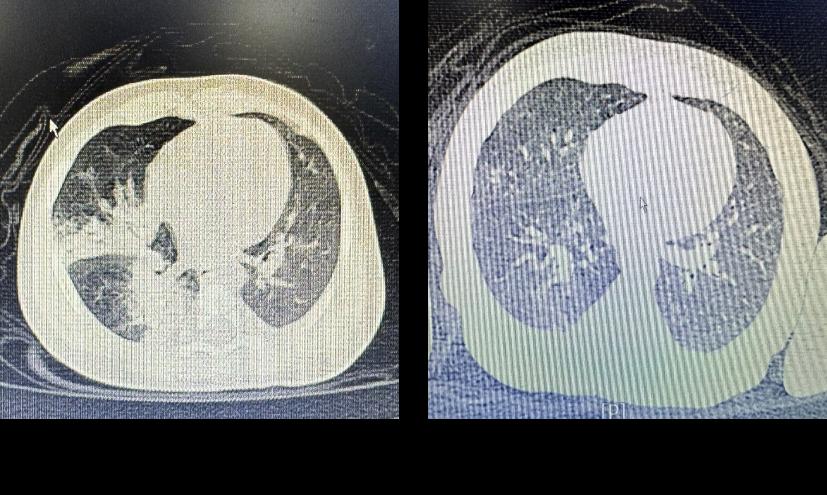

近期,我院小儿内科收治了一名仅58天的重症肺炎患儿,入院时患儿精神萎靡,高热不退,三凹征阳性,胸部CT右肺中叶及下治疗前治疗后叶均有实变。患儿年龄小,病情危重,入院后虽然给予抗感染治疗但症状无缓解,只有尽快解决患儿的肺实变,病情才会出现逆转。在制定了新的治疗方案后,王慧渊主治医师为患儿进行了支气管肺泡灌洗治疗。灌洗后,患儿的体温迅速下降,呼吸困难缓解,精神也明显好转。经过儿科医护的全力就治,患儿治愈出院。